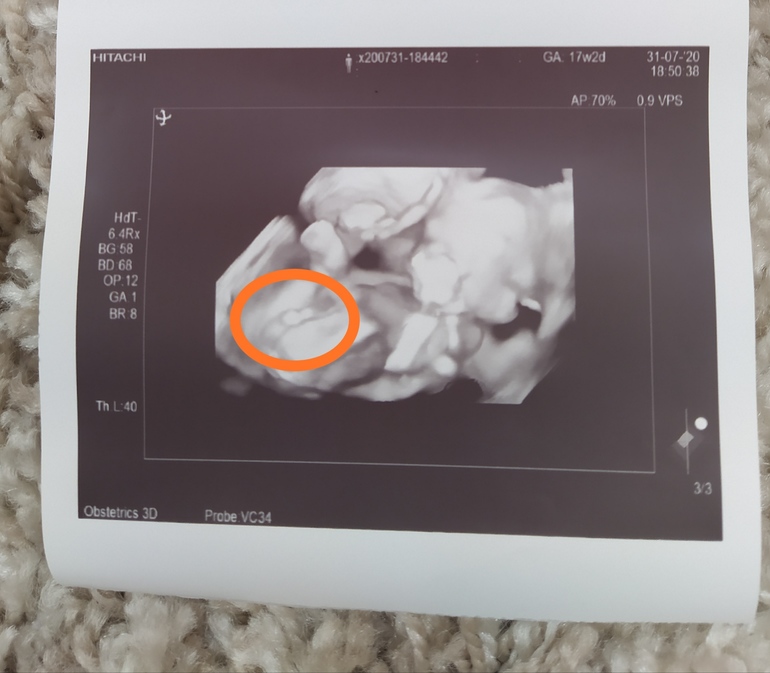

Сначала пообещали девочку, потом мальчика( фото прилагаю, но я думаю, что врач ошиблась), а сегодня малыш прятался и точно пол не сказали

Я, честно говоря, думала, что в Санкт-Петербурге такое вообще невозможно. Аппарат УЗИ хороший. Врач с опытом. Вот так и ошибаются с полом.

Да видно что аппарат хороший по снимку,я не так давно пост выкладывала там девушка выкладывала похожее фото и писала что по узи была девочка а родился мальчик вот так бывает..)